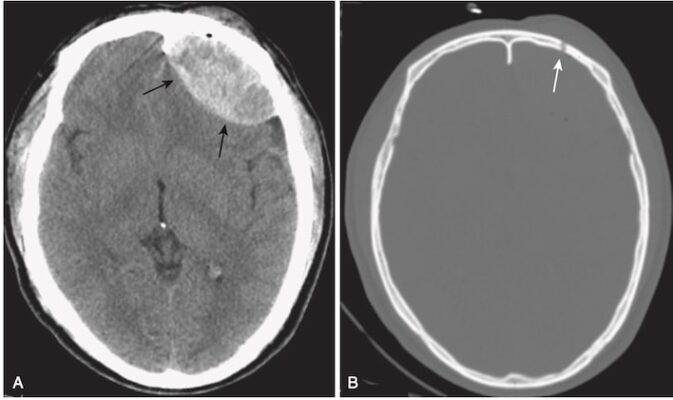

- Nhận biết tụ máu ngoài màng cứng:

- Máu tụ biểu hiện dưới dạng một khối hình thấu kính hai mặt lồi, đậm độ cao, thường thấy nhất ở vùng thái dương đỉnh của não (Hình 8).

- Vì màng cứng thường dính với vòm sọ (calvarium) ở mép các đường khớp sọ (sutures) nên máu tụ ngoài màng cứng không thể vượt quá các đường khớp sọ (máu tụ dưới màng cứng có thể vượt quá các đường khớp).

- Máu tụ ngoài màng cứng có thể vượt qua lều, nhưng máu tụ dưới màng cứng thì không.

- Nhận biết máu tụ dưới màng cứng cấp tính (Hình 9)

- Trên CT, máu tụ dưới màng cứng cấp tính có hình lưỡi liềm, các dải ngoài não có đậm độ cao có thể băng ngang các đường khớp sọ và vào khe liên bán cầu. Máu tụ không vượt qua đường giữa.

- Điển hình, máu tụ dưới màng cứng lõm vào trong về phía não (máu tụ ngoài màng cứng lồi vào trong) (xem Hình 9, A).

- Sau một thời gian và khi máu tụ chuyển sang bán cấp, hoặc nếu máu dưới màng cứng được trộn với dịch não tủy có độ đậm đặc thấp hơn, chúng có thể biểu hiện đồng tín hiệu/cùng đậm độ (isodense) so với phần còn lại của não, trong trường hợp đó cần tìm các rãnh não bị ép hoặc biến mất hoặc bị đẩy lệch khỏi mặt trong xương sọ như các dấu hiệu của SDH (xem Hình 9, B).

- Các máu tụ dưới màng cứng có thể biểu hiện một mức dịch- dịch sau 1 tuần, khi các tế bào lắng xuống dưới huyết thanh.

- Máu tụ dưới màng cứng mạn tính thường có đậm độ thấp so với phần còn lại của não (xem Hình 9, C).